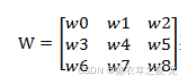

为了为医学体绘制研究工作提供更为清晰、准确、无误的CT图像。本文提出了改进的边缘增强的中值滤波方法对原始的医学CT图像进行处理。文中采用3x3的滤波窗1:3,处理的CT图像是灰度级为256的灰度图像,3x3的灰度矩阵w为:

其中wi为无符号数,wi∈[0,256],i∈[0,8]的整数。

在传统的中值滤波方法中,就是直接对w0~w8。进行排序,然后取中间的值作为该像素的灰度值.这样边缘信息就会被削弱。为了增强边缘信息。针对矩阵构造一个中间矩阵M: